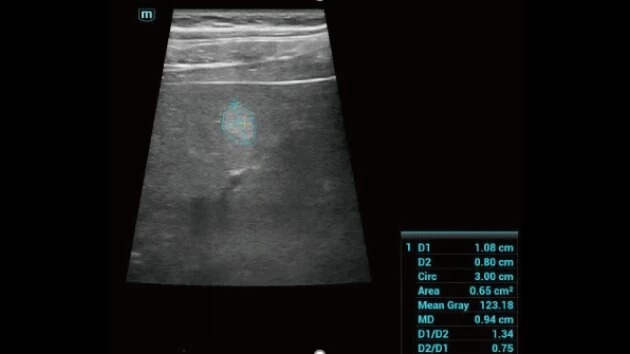

Ультразвуковой аппарат Mindray Consona N7 принадлежит к категории устройств экспертного класса и предназначен для проведения широкого спектра общей диагностики. Благодаря высокому уровню визуализации, он активно применяется в кардиологии, а также для гинекологических исследований.

Mindray Consona N7 представляет собой передовую диагностическую систему, созданную для ежедневного клинического использования с акцентом на высокое качество визуализации.

• Высокое разрешение изображений для точной диагностики

• HD Scope технология для увеличения пространственного разрешения в зоне интереса